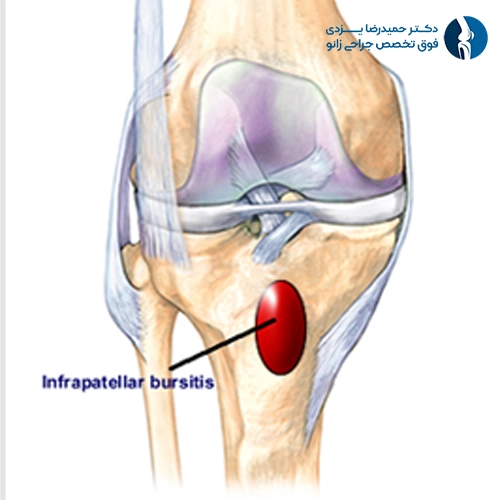

بورسیت پسکشککی (Infrapatellar Bursitis)

در این نوع، کیسه بورس در زیر استخوان کشکک ملتهب میشود. این بورس در بین تاندون پاتلار و استخوان درشتنی قرار دارد و به حرکت روان زانو در حین خم و راست شدن کمک میکند. التهاب در این ناحیه اغلب بهدلیل پرشهای مکرر یا فشارهای عمودی شدید ایجاد میشود، از اینرو به آن «زانوی کشیش» یا Clergyman’s knee نیز میگویند.

علائم شامل درد در قسمت جلوی زانو، کمی پایینتر از کشکک، و تورم موضعی است. گاهی ممکن است بهخاطر شباهت علائم با تاندونیت پاتلار اشتباه گرفته شود. درد در حالت نشستن طولانیمدت یا بالا رفتن از پلهها نیز شایع است.

درمان معمولاً شامل اجتناب از فعالیتهای تشدیدکننده، استفاده از زانوبند، داروهای ضدالتهاب و تمرینات فیزیوتراپی برای تقویت عضلات اطراف زانوست. در موارد مقاوم، ممکن است تزریق کورتون انجام شود.